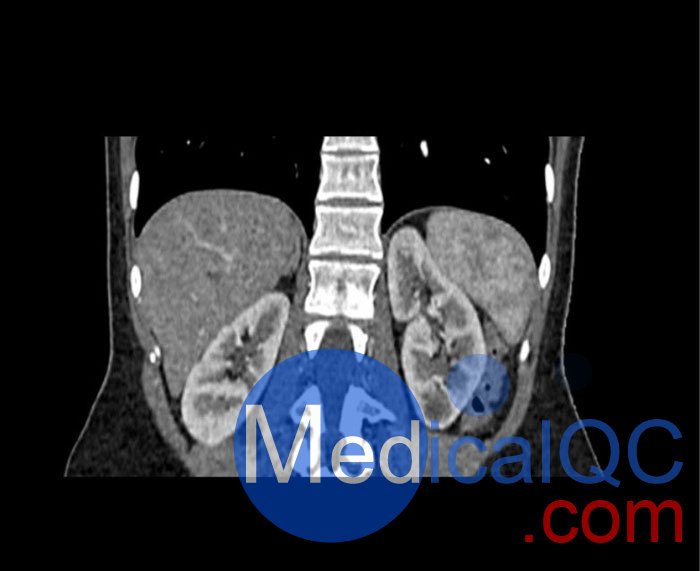

WEK53-01腹部模體,WEK53-01動脈期腹部模體,WEK53-01腹部模型模擬了動脈期的造影劑增強腹部。它覆蓋了第十一胸椎至第四腰椎(部分包括在內)。

該模型可用于 CT(包括 CBCT)以評估和優化成像性能和后處理應用,包括支持 AI 的應用。它也適用于培訓目的。

該模型提供了對軟組織和骨組織的詳細而逼真的模擬。空隙中填充著約-160HU的纖維素-聚合物復合材料。